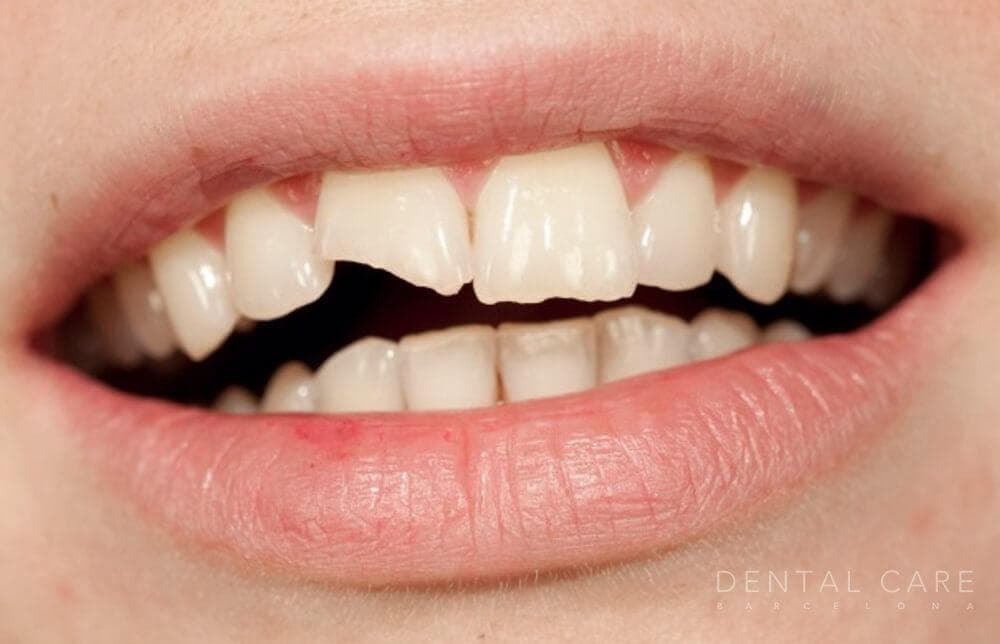

Diente fracturado

Diente roto, partido o astillado por golpe o accidente.